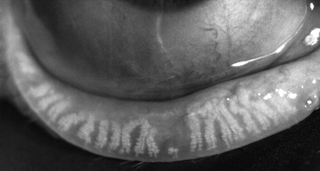

et des abcès de la cornée. Au stade ultime des ulcères de cornée

et des kératites filamenteuses peuvent apparaître.